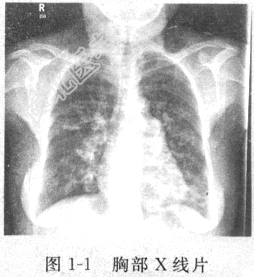

患者男性,40岁,因“反复咳嗽、咳痰十余年,加重伴发热、咯血1周”入院。门诊血常规示白细胞(WBC)15×10⁹/L,中性粒细胞百分比(N%)83.4%,血红蛋白(Hb)85g/L,胸部X线片(图1-1)示双肺纹理增多、紊乱,双肺可见多个不规则环状透亮阴影。查体:贫血貌,口唇发绀,杵状指(图1-2),无颈静脉怒张,双肺呼吸音粗,双下肺可闻及吸气相湿啰音,未闻及干啰音及哮鸣音,心浊音界无扩大,心率85次/分,律齐,未闻及病理性杂音,双下肢不肿。患者吸烟20年,400年支。入院诊断:支气管扩张症。